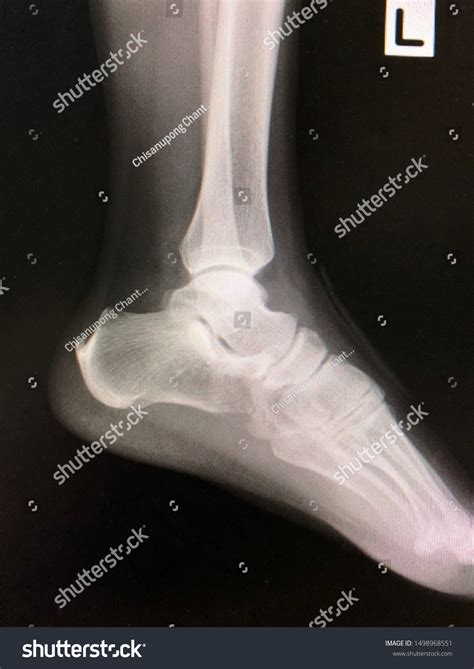

Lateral Ankle Xray

A Lateral Ankle Xray is a specific type of X-ray that provides a side view of the ankle. This view is particularly useful for assessing the alignment of the bones and identifying fractures or dislocations. The lateral view complements other views, such as the anteroposterior (AP) and mortise views, to give a comprehensive picture of the ankle's condition.

Interpreting a Lateral Ankle Xray requires a trained eye to identify key features and abnormalities. Some of the important aspects to look for include:

• Bone alignment: Ensuring that the bones are properly aligned and there are no signs of fractures or dislocations.

• Joint space: Assessing the width and uniformity of the joint space to detect any signs of arthritis or other joint issues.

• Soft tissue swelling: Identifying any swelling or inflammation around the ankle that may indicate an injury.

Radiologists and orthopedic specialists are trained to interpret these images and provide a detailed report of their findings. This report is then used to guide treatment decisions.

Some of the common findings on a Lateral Ankle Xray include:

• Fractures: Visible breaks in the bones, which may be simple or complex.

• Dislocations: Misalignment of the bones, often due to severe trauma.

• Osteoarthritis: Changes in the bone structure and joint space indicative of degenerative joint disease.

• Soft tissue swelling: Inflammation or edema around the ankle, which may be due to injury or infection.